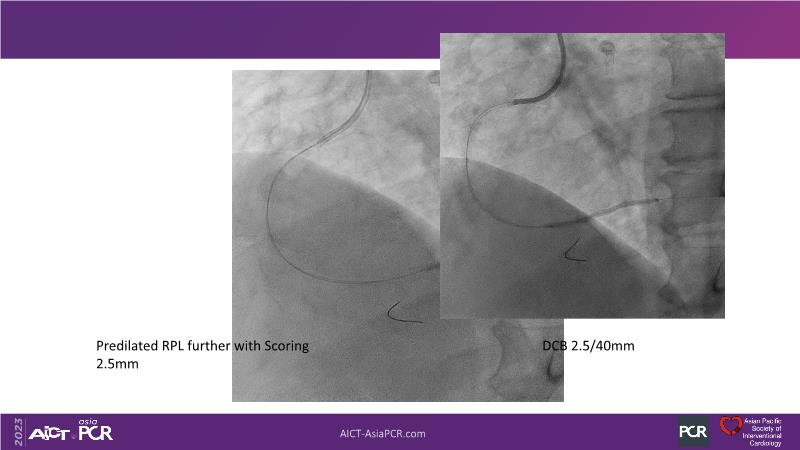

Leave nothing behind: DCB-only PCI strategy - How DCB evidence has changed today's practice?

This session offers an opportunity to stay informed about the recent developments in the International DCB Consensus Group, gain insights into the latest clinical data and real-world experiences related to drug-coated balloon (DCB)-only PCI, understand the safety aspects of DCB in managing complex PCI cases, and participate in an interactive discussion with experts.